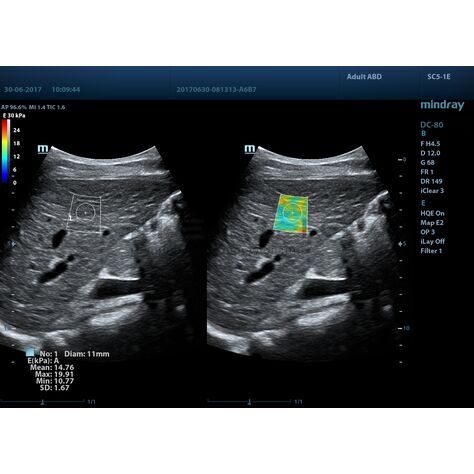

Программное обеспечение для оценки эластичности ткани методом эластографии сдвиговой волны (метод 2D-с формированием двухмерной цветовой эластограммы и количественной оценкой эластичности) на линейных и конвексных датчиках.

STE интегрирована с эксклюзивной технологией Ultra-Wide Beam Tracking от Mindray для двумерной эластографии сдвиговой волной в реальном времени. Специализированные измерительные инструменты позволяют проводить количественный анализ модуля упругости с высокой точностью.

Опция работает:

• на линейных датчиках

• на конвексных датчиках